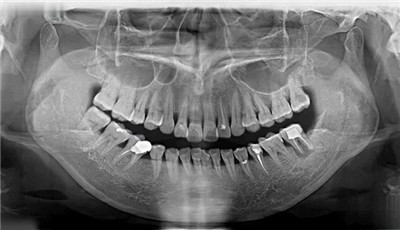

对颌牙伸长、邻牙倾倒、余牙移位……时间越久,咬合关系破坏越严重,当单颗缺牙演变为多颗、半口时,咬合重建的难度就大多了。

2. 牙槽骨流失严重,可能要植骨

通常情况下,牙齿脱落或被拔除后的数周至数月内,缺牙窝没有牙根刺激,牙槽骨会逐渐流失,存在萎缩的现象,进而导致牙骨量不太能支撑起种植牙体的固定。

为了让种植体站得稳,就需要骨粉骨膜,甚至植自体骨。因此,在种牙手术之前,都需要对牙槽骨情况进行评估。